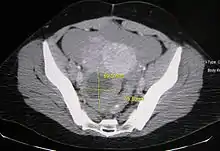

Ovarian cysts are usually diagnosed by ultrasound, CT scan, or MRI, and correlated with clinical presentation and endocrinologic tests as appropriate.[10]

Ovarian cysts are considered large when they are over 5 cm and giant when they are over 15 cm. In children, ovarian cysts reaching above the level of the umbilicus are considered giant.